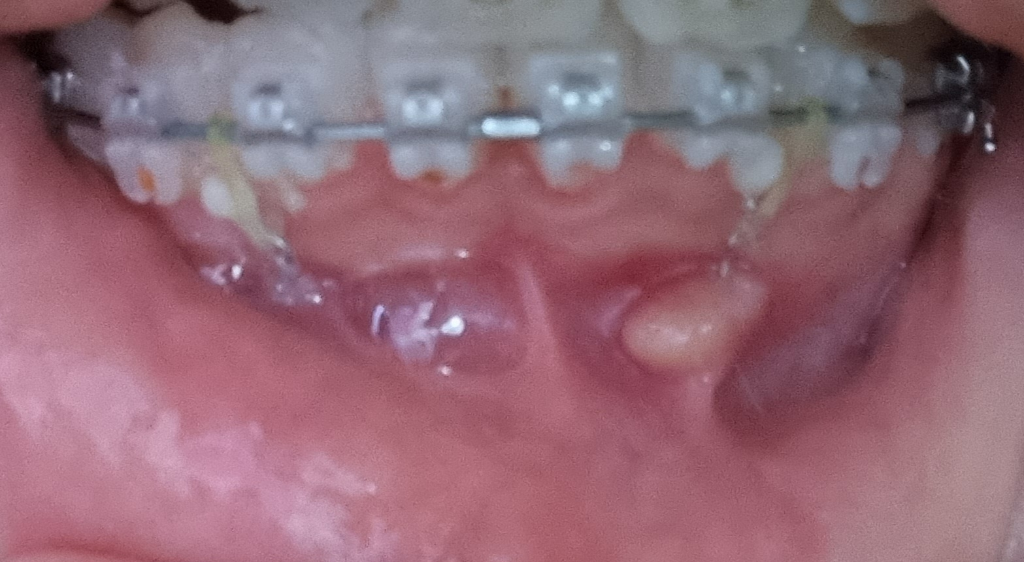

해당 부위가 과도하게 자극되어 나타난 일시적인 잇몸 증식으로 보여집니다. 스크류를 제거하거나 다른 부위에 식립하고 힘의 방향을 조금 조절해야 할 것으로 보입니다. 치과 방문을 하는 것이 좋으며 일반적인 양상은 아닙니다.

아마도 잇몸이 과증식된거 같습니다.교정을 하시고 그쪽이 계속 어떤 자극을 받아서 그러는거 같으며 크게 문제가 잇는건 아닙니다. 나중에 마취하시고 제거를 하시면됩니다.

미니스크류 주변으로 염증이 생긴것 같습니다..제거후 회복이 되면 재식립할 가능성이 있습니다.